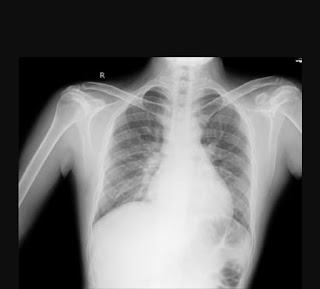

- In the x ray of the patient:

- There is no hyperinflation of the lung seen, hence COPD, Asthama can be ruled out.

- There is prominent bilateral pulmonary arteries indicating Pulmonary hypertension.